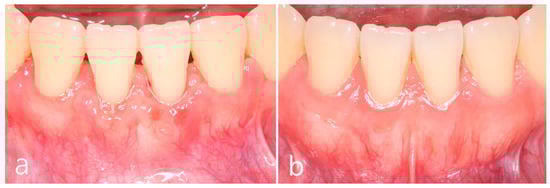

2. Case Report